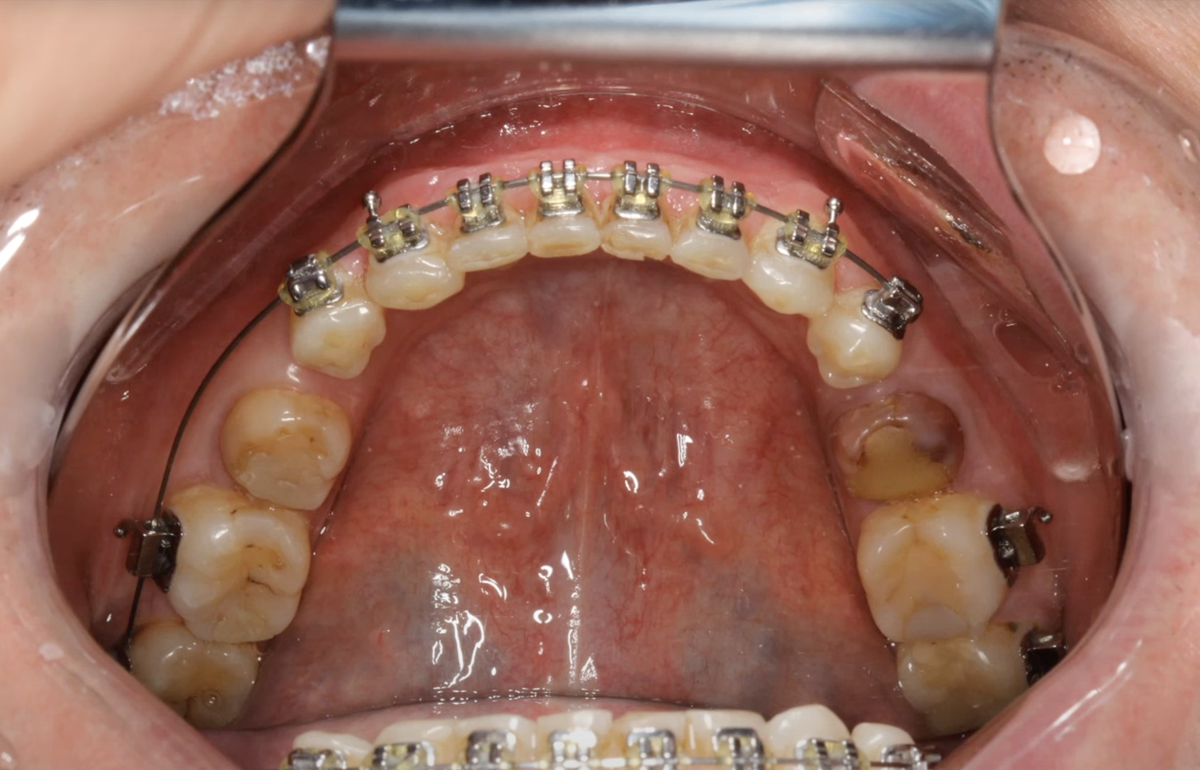

Сначала обратим внимание: у пациента в одной из областей челюсти образовалось большое пространство. Если посчитать зубы: один, два, три, четыре… и так далее до центральной линии — их почему-то оказалось девять.

А ведь должно быть всего семь! Ортодонт зачем-то создал место ещё под два премоляра.

Верхняя челюсть пациента

Итог: три с половиной года лечения до прихода ко мне — и непонятный результат.